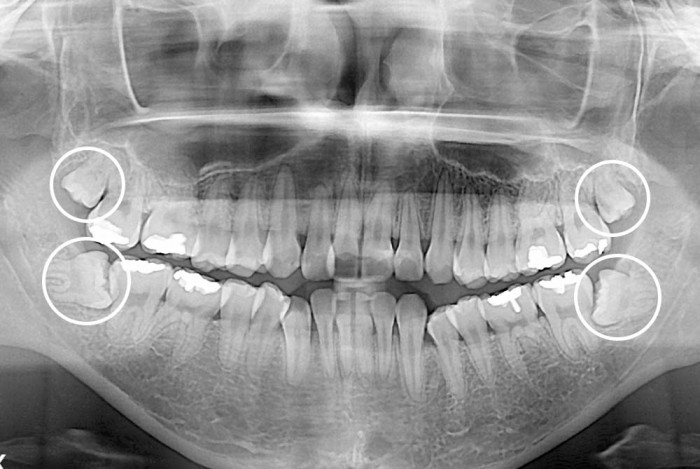

[사랑니] 사랑니

치료전 : 2015-02-24

세종치과는 구강악안면외과학 박사이신 원장님이 발치하는 치과입니다.